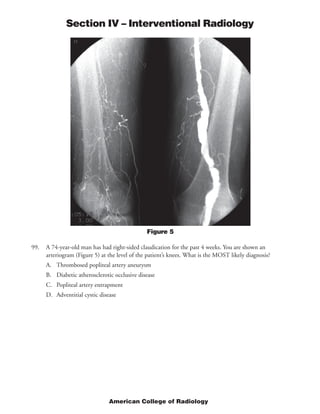

This document provides rationales for questions on the 2005 American College of Radiology Diagnostic In-Training Examination for interventional radiology residents. It includes the questions, images associated with some questions, findings for each image, and rationales for the correct answers. The questions cover topics such as locations of dialysis catheters, diagnoses for angiograms, standards for uterine artery embolization, and indications for percutaneous nephrostomy.